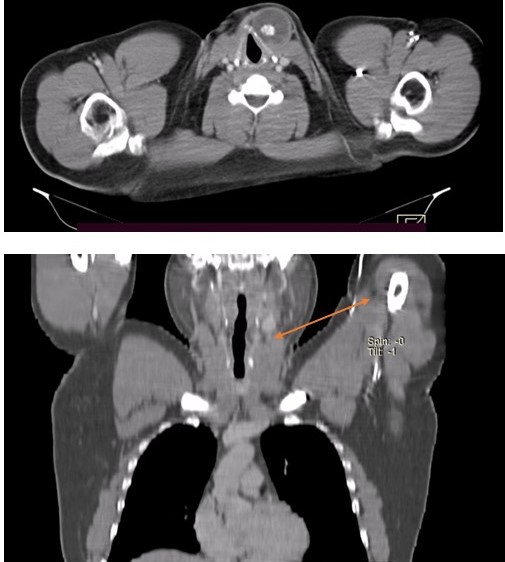

TC de cráneo, cuello, tórax, abdomen con contraste

Masa tumoral quística bien definida, encapsulada, con calcificación central en región latero-cervical izquierda, contacta el cartílago tiroides y se ubica por encima del polo superior del lóbulo tiroideo izquierdo, a evaluar mediante estudio histopatológico. No se descartan restos embrionarios, de tipo quiste desmoide (Figura 2a y 2b).

Adenopatía latero-cervical izquierda adyacente, a descartar origen secundario. Se sugiere estudio histopatológico.

Figura 2a y 2b. TC de cuello con contraste. Cabeza de flecha señalando la lesión quistica en región cervical, flecha señalando adenopatía en hemicuello izquierdo.